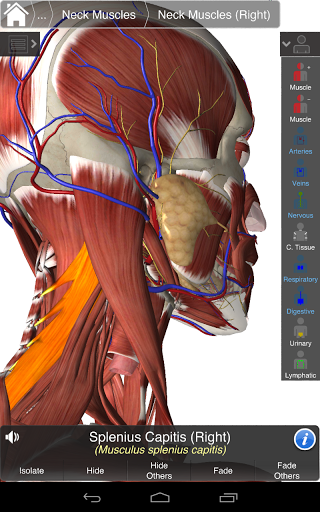

Essential Anatomy 3 représente la toute dernière technologie 3D révolutionnaire et un design innovant. Un moteur graphique 3D de pointe, construit sur mesure par 3D4Medical à partir de zéro, alimente un modèle anatomique très détaillé et fournit des graphiques de qualité exceptionnelle qu'aucun autre concurrent ne peut atteindre.

L'application représente une approche unique à l'apprentissage de l'anatomie générale. Les graphismes sont inégalés et rendent l'apprentissage, grâce à l'utilisation de contenu informatif et de fonctionnalités innovantes, une expérience riche et engageante.

Essential Anatomy 3 est réactif, visuellement magnifique et sans effort. L'application est entièrement 3D, ce qui signifie que vous pouvez voir n'importe quelle structure anatomique dans l'isolement, ainsi que de n'importe quel angle.

---- Corriger la prononciation audio pour chaque structure

---- Nomenclature latine pour chaque structure anatomique

---- Interface conviviale et intuitive